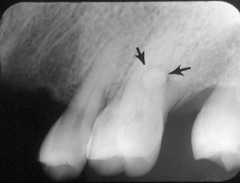

Mulberry Molars (see image)

irregularly shaped molars with poorly defined cusps also caused by syphilis

Mulberry Molars